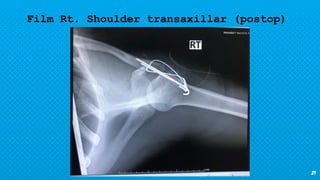

Film Rt. Shoulder transaxillar (postop)

21 Film Rt. Shouldertransaxillar (postop)